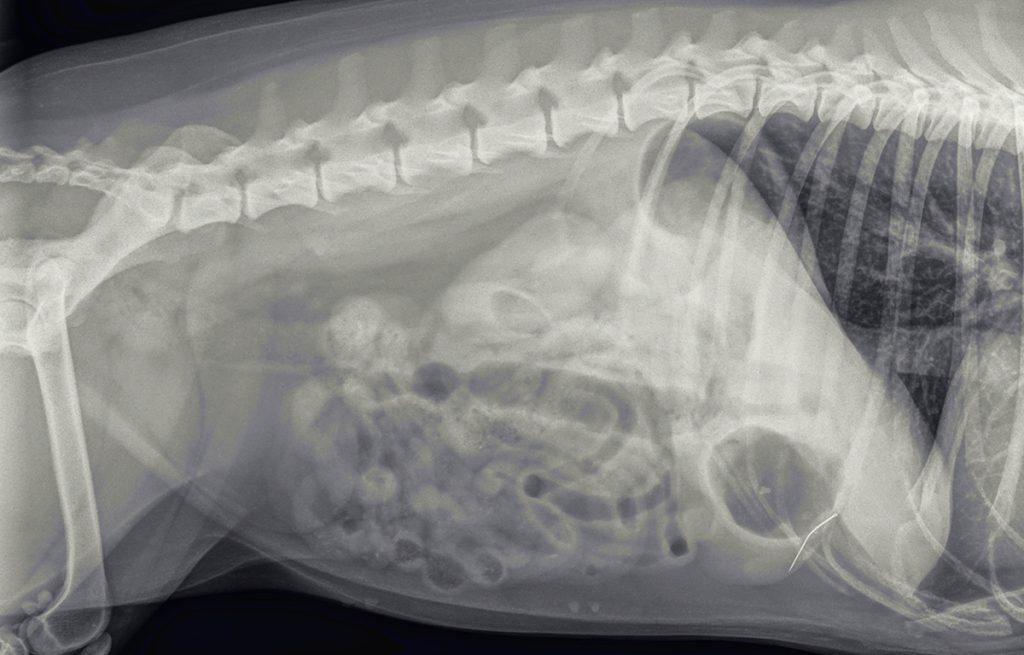

Ter controle, of de structuur nog in de buik aanwezig is, worden opnieuw röntgenfoto’s gemaakt. Hierop is het voorwerp nog goed zichtbaar, met een soort oogje erin. Het moet dus een naald zijn. De foto’s suggereren verder dat de naald niet in het maag-darmstelsel zit, maar in de buikholte.

Een paar dagen later is het zo ver. We maken voor de zekerheid opnieuw foto’s, om de juiste lokatie te controleren. De naald lijkt aardig op dezelfde plek te liggen.

We zullen nooit helemaal zeker weten hoe de naald in de buikholte terecht is gekomen. Gezien de localisatie, de richting, het zwart zijn en het ontbreken van uitgebreide ontsteking er omheen is de gedachte dat hij in de maag gezeten heeft. Hier is hij door het maagzuur zwart geworden en steriel geworden. Waarschijnlijk is hij daarna door een maagbeweging door de wand heen gestoken. Lady heeft wat dat betreft veel geluk gehad; zou de naald de galblaas geraakt hebben of een groot bloedvat, dan was het anders afgelopen.